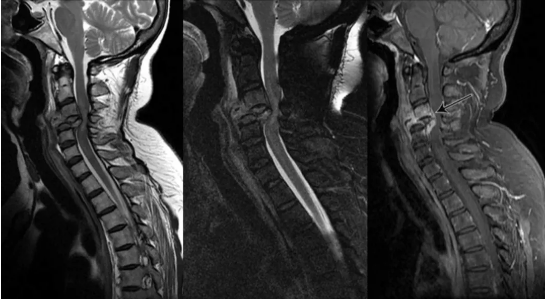

3.脊髓型颈椎病

(1)临床上出现颈脊髓损害的表现。多数患者首先出现一侧或两侧下肢麻木、沉重感,随后逐渐出现行走困难,下肢肌肉发紧,随后出现行走困难,严重者步态不稳、行走困难,双脚有踩棉花感。

部分患者可出现膀胱和直肠功能障碍。如排尿困难、尿频、尿急等

(2)X线片上显示椎体后缘骨质增生、椎管狭窄。影像学证实存在脊髓压迫。

(3)除外肌萎缩性侧索硬化症、脊髓肿瘤、脊髓损伤、多发性末梢神经炎等。